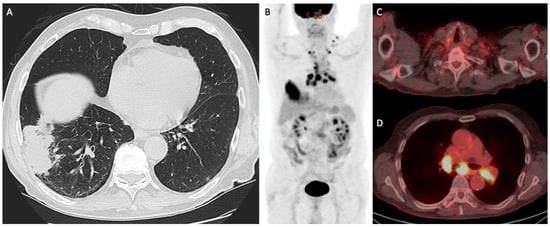

- Liu, J.; Dong, M.; Sun, X.; Li, W.; Xing, L.; Yu, J. Prognostic Value of 18F-FDG PET/CT in Surgical Non-Small Cell Lung Cancer: A Meta-Analysis. PLoS ONE 2016, 11, e0146195. [Google Scholar] [CrossRef]

- Paesmans, M.; Berghmans, T.; Dusart, M.; Garcia, C.; Hossein-Foucher, C.; Lafitte, J.J.; Mascaux, C.; Meert, A.P.; Roelandts, M.; Scherpereel, A.; et al. Primary tumor standardized uptake value measured on fluorodeoxyglucose positron emission tomography is of prognostic value for survival in non-small cell lung cancer: Update of a systematic review and meta-analysis by the European Lung Cancer Working Party for the International Association for the Study of Lung Cancer Staging Project. J. Thorac. Oncol. 2010, 5, 612–619. [Google Scholar] [CrossRef]

- Im, H.J.; Pak, K.; Cheon, G.J.; Kang, K.W.; Kim, S.J.; Kim, I.J.; Chung, J.K.; Kim, E.E.; Lee, D.S. Prognostic value of volumetric parameters of 18F-FDG PET in non-small-cell lung cancer: A meta-analysis. Eur. J. Nucl. Med. Mol. Imaging 2015, 42, 241–251. [Google Scholar] [CrossRef] [PubMed]

- Wang, L.; Tang, G.; Hu, K.; Liu, X.; Zhou, W.; Li, H.; Huang, S.; Han, Y.; Chen, L.; Zhong, J.; et al. Comparison of 68Ga-FAPI and 18F-FDG PET/CT in the Evaluation of Advanced Lung Cancer. Radiology 2022, 303, 191–199. [Google Scholar] [CrossRef] [PubMed]

- Zhou, X.; Wang, S.; Xu, X.; Meng, X.; Zhang, H.; Zhang, A.; Song, Y.; Zhu, H.; Yang, Z.; Li, N. Higher accuracy of [68 Ga]Ga-DOTA-FAPI-04 PET/CT comparing with 2-[18F]FDG PET/CT in clinical staging of NSCLC. Eur. J. Nucl. Med. Mol. Imaging 2022, 49, 2983–2993. [Google Scholar] [CrossRef]

- Tylski, E.; Goyal, M. Low Dose CT for Lung Cancer Screening: The Background, the Guidelines, and a Tailored Approach to Patient Care. Mo. Med. 2019, 116, 414–419. [Google Scholar] [PubMed]

- National Lung Screening Trial Research Team; Aberle, D.R.; Adams, A.M.; Berg, C.D.; Black, W.C.; Clapp, J.D.; Fagerstrom, R.M.; Gareen, I.F.; Gatsonis, C.; Marcus, P.M.; et al. Reduced lung-cancer mortality with low-dose computed tomographic screening. N. Engl. J. Med. 2011, 365, 395–409. [Google Scholar] [CrossRef]